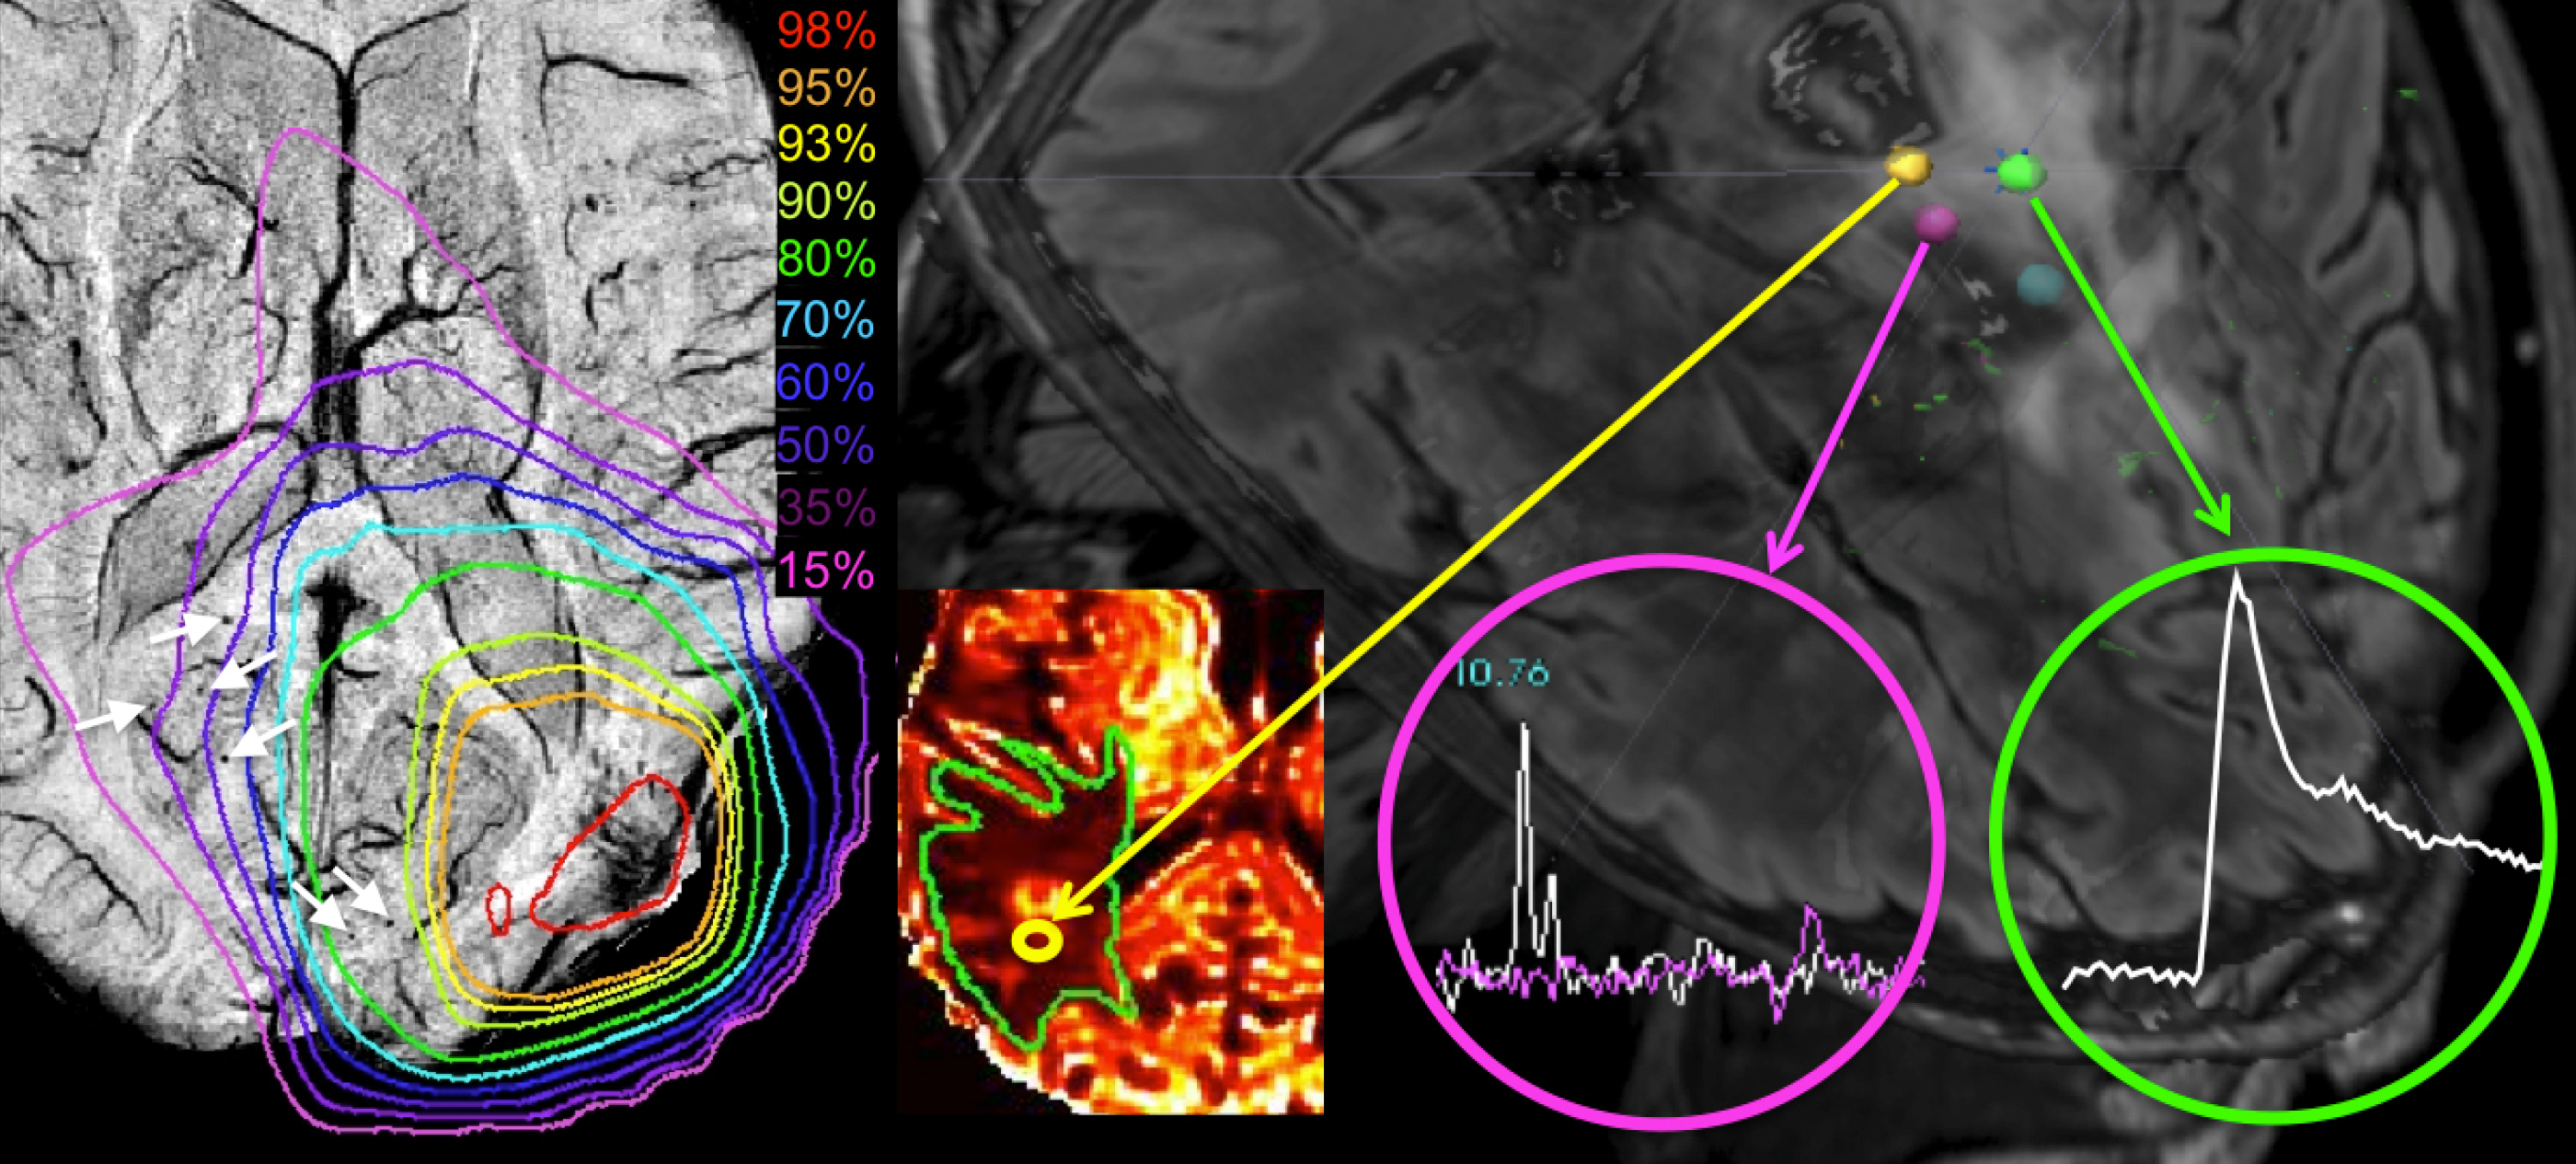

MRI composite image showing the effects of radiation therapy on brain vasculature and mapping of image-guided tissue samples.

Our group is focused on developing novel methods for acquisition, reconstruction, post-processing, and quantitative analysis of Magnetic Resonance (MR) brain images. Using a combination of multiparametric structural, physiological, and metabolic MRI techniques, our goal is to quantitatively characterize heterogeneity within malignant brain tumors, monitor response to novel treatment regimens, and investigate the long-term effects of therapy on healthy brain tissue structure and cognitive function. As part of the Surbeck Laboratory for Advanced Imaging, we are based in Byers Hall at the UCSF Mission Bay campus and have access to state-of-the-art 3T and 7T human research scanners.  Many of the methodologies we develop initially to evaluate patients with brain tumors are also being applied to other neurological diseases.

• Guanzhong Su was a graduate student in the Master of Science in Biomedical Imaging (MSBI) program at UCSF. His research was focused on developing a pipeline for integration of metabolic and physiology imaging into clinical workflow for radiation treatment planning for glioblastoma (GBM) patients.

• Paul Rowley was a Clinical Research Coordinator. Born in San Francisco and raised in Madison, Wisconsin, Paul joined the Lupo Lab in 2017 while studying medicine at the University of Wisconsin School of Medicine and Public Health (class of 2022). His research interests included applying diffusion tensor imaging (DTI) and quantitive susceptibility mapping (QSM) to study Huntington’s disease; developing and comparing QSM reconstruction methodologies; and using multiparametric imaging to improve radiotherapy planning for patients with glioblastoma multiforme.